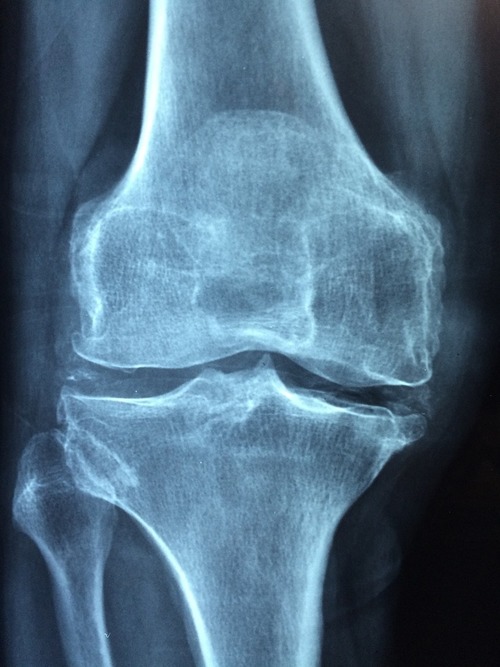

Osteoarthritis Biomarker Detected Using Nanotechnology

Scientists measure a specific molecule indicative of osteoarthritis and a number of other inflammatory diseases using a newly developed technology